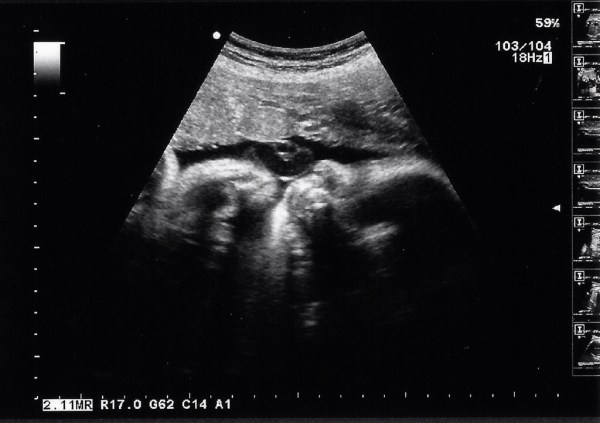

I could tell from the beginning that the sonographer was going to be very thorough and she talked us through everything she was doing. She started measuring him head circumference and showed us his little face. It looked almost as clear as a 3D scan, seeing his eyes closed with his chubby cheeks – unfortunately she didn’t take a photo of this so the scan photos I got weren’t anything like as clear as this.

She then moved on and measured his kidneys and femur length. She had to ask me to roll onto my side to try to get him to move a little bit so she could measure his abdominal circumference but it did the trick and she managed to get the measurement. She again checked that he was a boy – definitely! No one could mistake that! She went on and measured fluid levels and they were all normal. She showed us his feet and told us he had lots of hair (I am going to take her word for that, I couldn’t make that out but she pointed out what showed this) she then went on to say something that has been worrying me since I read the scan report, but that she glossed over at the time, that my placenta was mature. She said at the time that it was normal, but mentioned it in the scan notes. From a little bit of internet research it doesn’t seem to be abnormal, but not ideal. I shall make sure I keep an extra close eye on his movements from now on (not that I wasn’t already) and will ask my midwife at my next appointment to clarify how serious I should be taking this.